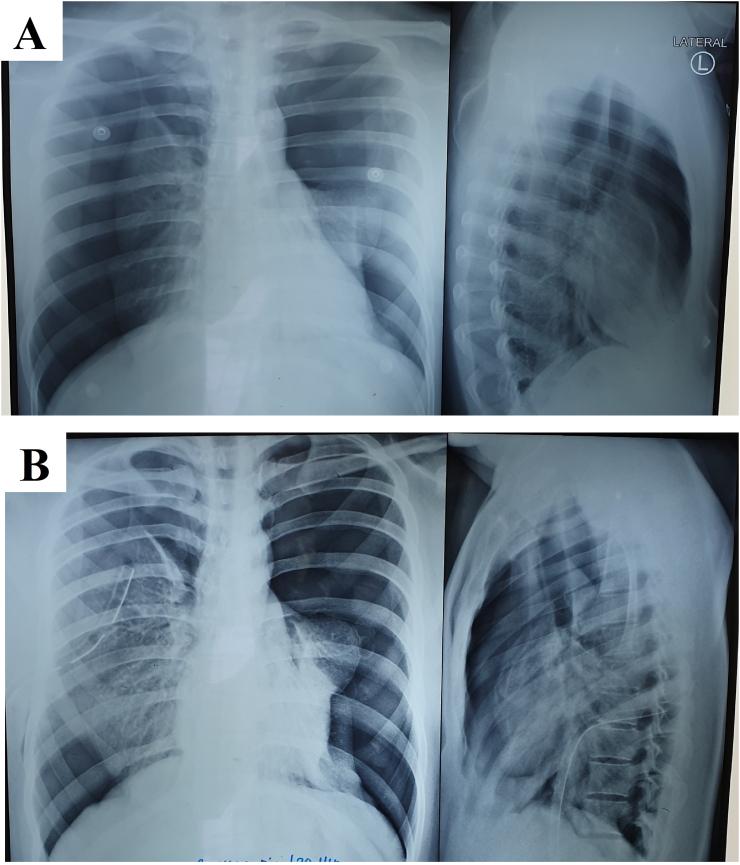

A 20-year-old man with a complaint of shortness of breath is suspected of having PSP and tuberculosis. The patient underwent water seal drainage installation in both lung cavities, but showed no improvement. Multiple blebs were found after a few days. A wedge resection with VATS became an option. The patient had improved lung function after the procedure.

The WSD installation showed lungs improvement. However, when trained for lung expansion, the lung condition became bad. After wedge resection with the help of VATS on multiple blebs, the lung had a significant improvement.